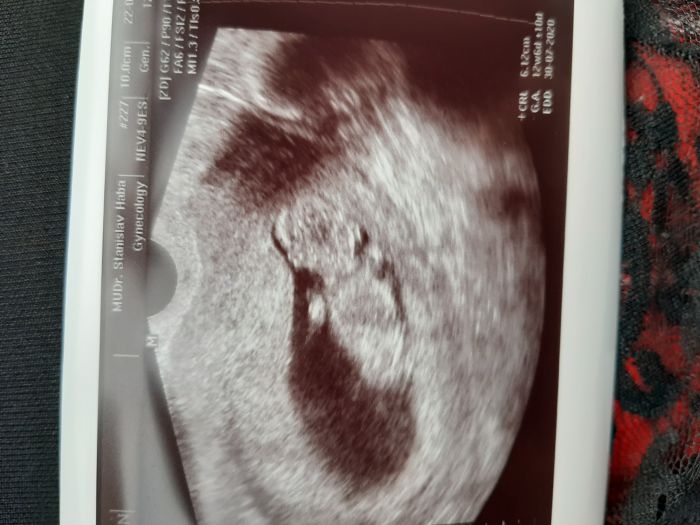

Tak já dnes byla v poradně.. mám nového gynekologa.Predchozí 3těhu u jiného lékaře celkem 3-4ultrazvuky.Tento mi ho dělá pokaždé v poradně.Někde jsem četla je to není dobré pro mimi.Slyšela jste některá o tom něco?A jak to máte vy?Jinak dnes ho měřil a bylo větší 12+6 přitom jsem 12+1.Vrtělo se zprava doleva..tak to treba bylo tím.Holky a na jaký jdete screning?Obyčejný nebo si necháte udělat ty lepší testy?Já mám v plánu rozšířený Harmony..výsledky jsou 99.8%.Doktor říkal.. ze když to vyjde dobře..nebude mě posílat v tom 16tt na tripletest.Chtěla bych udělat 3D ulz..jesťě jsem ho nikdy neměla.Teď jsem se dívala na netu na obrázky z 13tt a jsou úzasný.Jak to máte v plánu vy??Přikládám foto mimíska z dneška?

Já jdu zítra na krev a 5.2. na velký screening. Takže krev je a už mi dělá vždy. Mám i z každého fotku. Ale říkal že ty tisknutí jsou méně kvalitní, že je mám fotit telefonem. Nemyslím si že by to bylo úplně nezdravé pro mimi. Když jdu sednout s manželem do hospody je to určitě více nezdravé. A 3d ultrazvuk asi nechci moc se mi to nelíbí. Přijde mi to zbytečný. A Kači a ty jsi mi ukradla fotku dítěte že ? Teda já jsem ofiko 12 +3 ale podle už 10+3 těším se na screening. Zle mi je stejně zle ale už se na malého těšíme a říkáme to postupně rodině. Doufám že to bude holčička mám šílený akné.. Tak uvidíme. Myslím na vás holky. Jste dobrá podpora.. Moc tady kamarády nemám. Posílám vám fotky malého flíčku